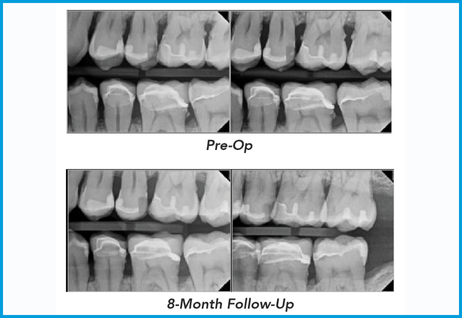

Introduction Solea® Perioguide™ is a minimally invasive laser therapy designed to effectively treat periodontitis while reducing patient discomfort and accelerating healing.1,2,3 This case highlights how the protocol provided rapid resolution of bleeding and inflammation and significant pocket depth reduction. It furth...

Introduction Solea® Perioguide™ is a minimally invasive laser therapy designed to effectively treat periodontitis while reducing patient discomfort and accelerating healing.1,2,3 This ...